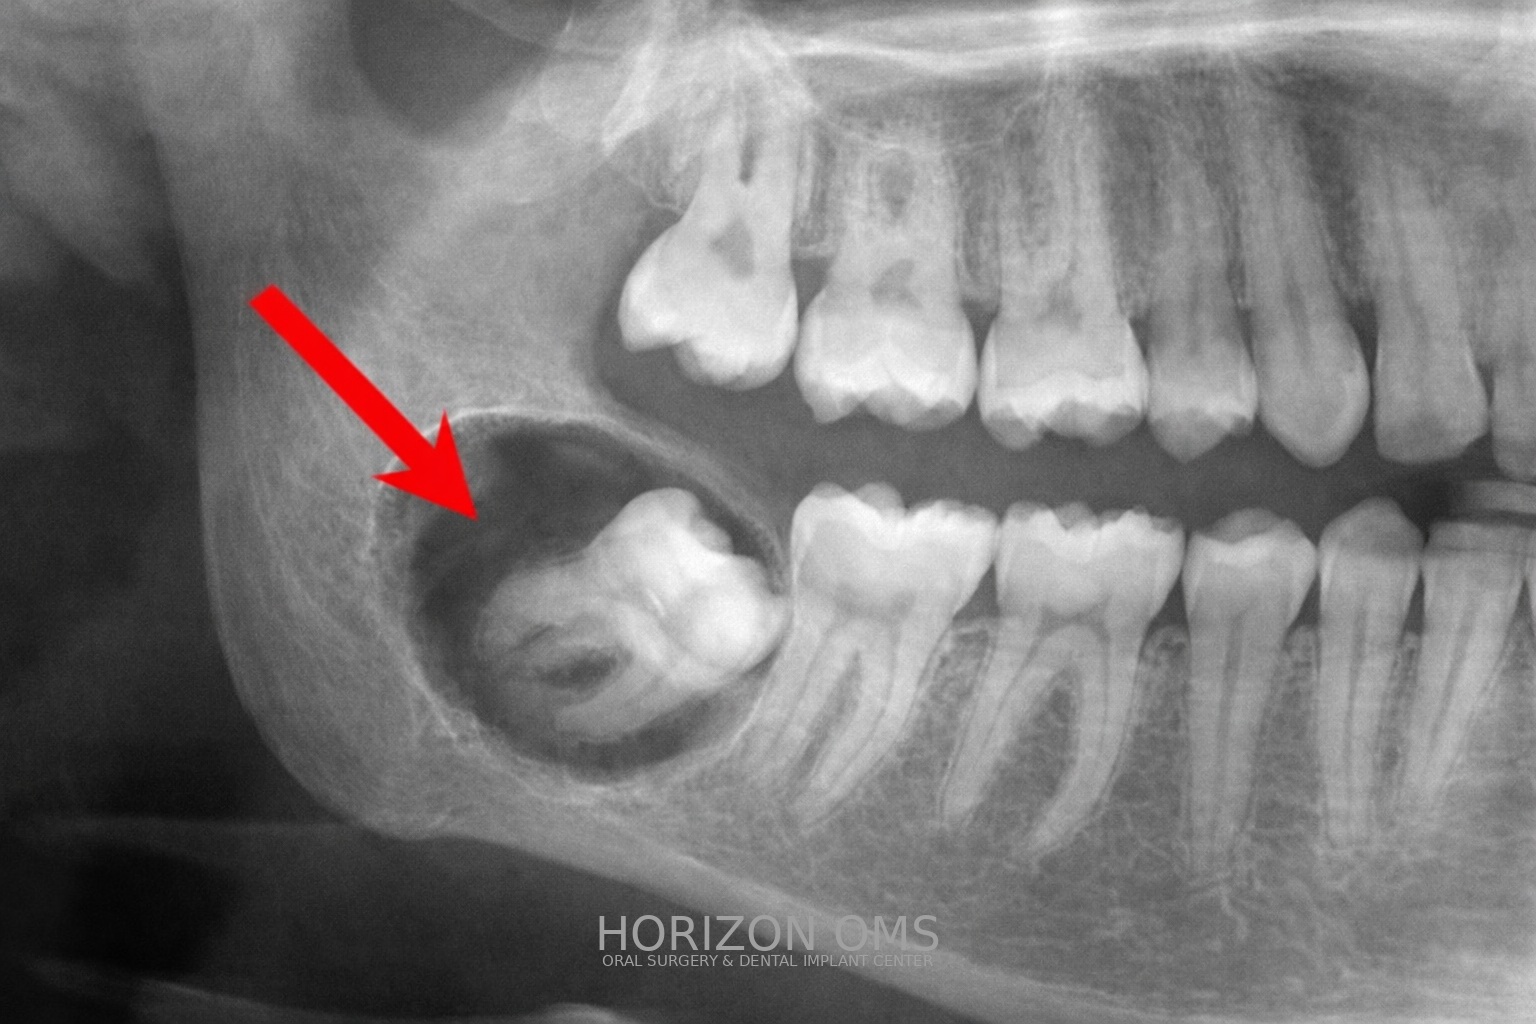

• Jaw bone: lesions within the bone (commonly referred to as cysts). We typically review imaging (often CBCT when helpful) to plan a safe approach and determine whether an in-office procedure or sedation is best.

• Radiographic findings in the jaw that need clarification